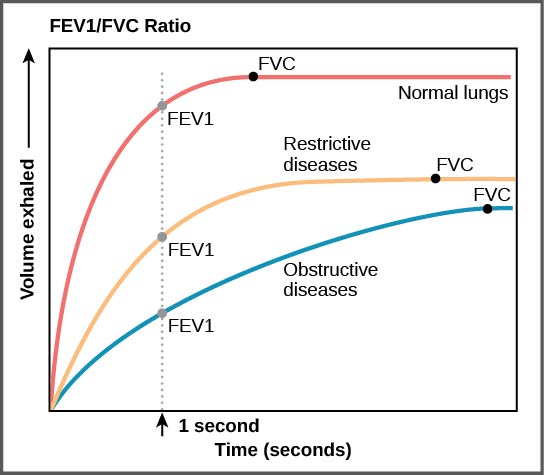

Pulmonary diseases reduce the rate of gas exchange into and out of the lungs. Two main causes of decreased gas exchange are compliance (how elastic the lung is) and resistance (how much obstruction exists in the airways). A change in either can dramatically alter breathing and the ability to take in oxygen and release carbon dioxide.

Examples of restrictive diseases are respiratory distress syndrome and pulmonary fibrosis. In both diseases, the airways are less compliant and they are stiff or fibrotic. There is a decrease in compliance because the lung tissue cannot bend and move. In these types of restrictive diseases, the intrapleural pressure is more positive and the airways collapse upon exhalation, which traps air in the lungs. Forced or functional vital capacity (FVC), which is the amount of air that can be forcibly exhaled after taking the deepest breath possible, is much lower than in normal patients, and the time it takes to exhale most of the air is greatly prolonged (Figure). A patient suffering from these diseases cannot exhale the normal amount of air.

Obstructive diseases and conditions include emphysema, asthma, and pulmonary edema. In emphysema, which mostly arises from smoking tobacco, the walls of the alveoli are destroyed, decreasing the surface area for gas exchange. The overall compliance of the lungs is increased, because as the alveolar walls are damaged, lung elastic recoil decreases due to a loss of elastic fibers, and more air is trapped in the lungs at the end of exhalation. Asthma is a disease in which inflammation is triggered by environmental factors. Inflammation obstructs the airways. The obstruction may be due to edema (fluid accumulation), smooth muscle spasms in the walls of the bronchioles, increased mucus secretion, damage to the epithelia of the airways, or a combination of these events. Those with asthma or edema experience increased occlusion from increased inflammation of the airways. This tends to block the airways, preventing the proper movement of gases (Figure). Those with obstructive diseases have large volumes of air trapped after exhalation and breathe at a very high lung volume to compensate for the lack of airway recruitment.